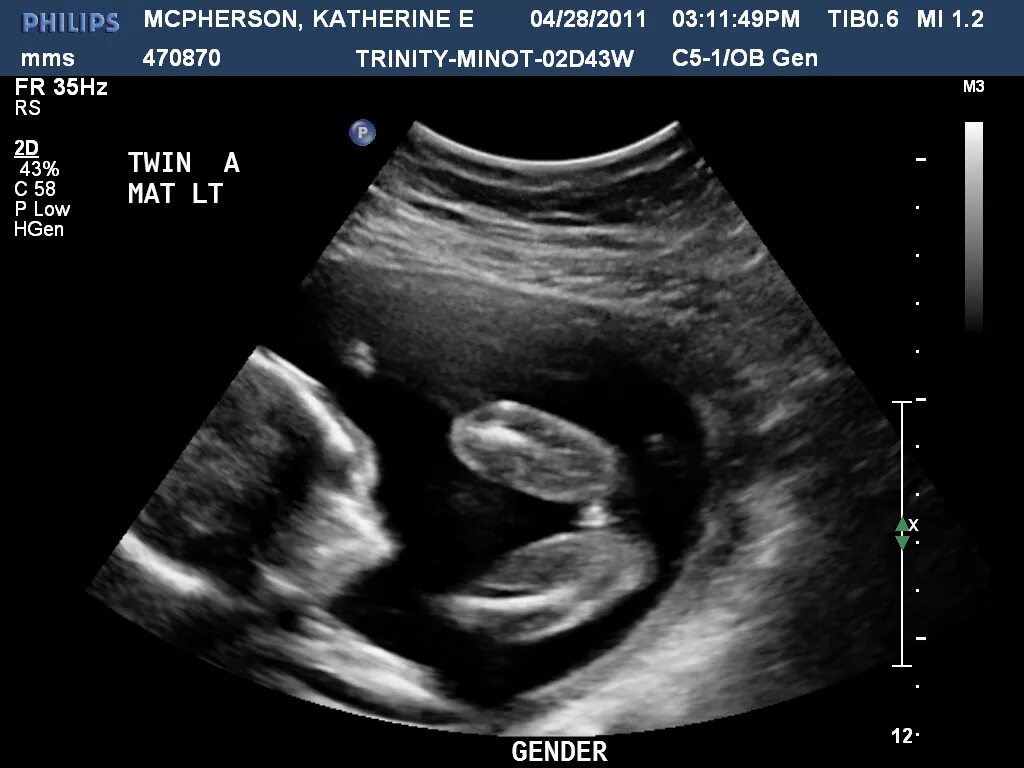

16 неделя можно ли узнать пол ребенка